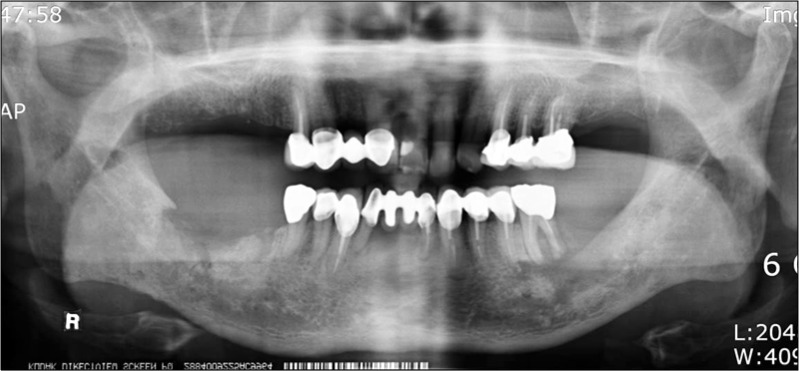

Fig. 1.

Panoramic view on first visit: 3 months after extraction of #46, 47.